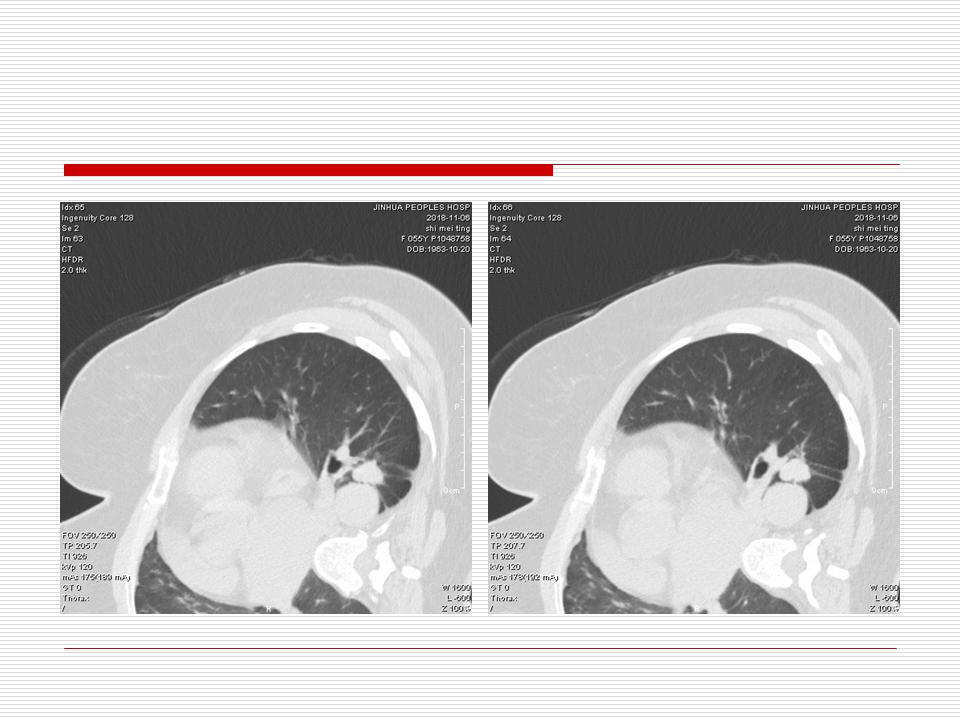

肺部阴影永恒且最重需要鉴别的是:到底是炎症还是肿瘤?但临床的病例中的影像表现难以界定或有些肿瘤特征,同时又有些炎症特点是非常常见的情况。作为临床医生我们怎么去总结分析,并找到之所以是炎症或之所以是肿瘤的细微差别或特点非常重要,也非常有用。2019.12.7浙江省2019年胸心外科学学术年会在宁波召开时,我的临床病例分析与经验总结<那些像肺癌的炎症与像炎症的肺癌>获得在大会交流的机会,以下为该PPT的内容,与你分享,希望对同道有益,有借鉴与启迪。若有探讨与进一不完善的建议,欢迎文末留言讨论: